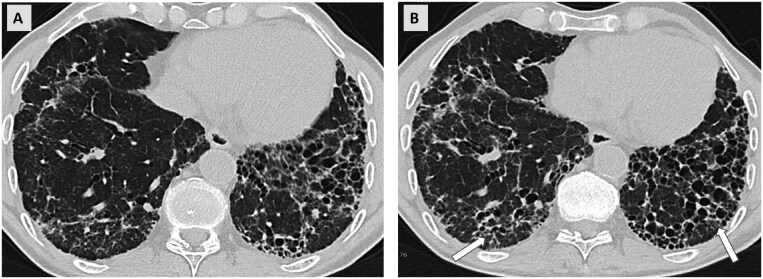

A subset of patients with interstitial lung diseases (ILDs) experiences disease progression despite standard treatment protocols. Similar to idiopathic pulmonary fibrosis, the archetype of progressive fibrotic ILDs, these patients exhibit worsening clinical symptoms, declining lung function, and progressive radiological changes, often resulting in shortened survival. This progressive disease pattern is classified under the term progressive pulmonary fibrosis or progressive fibrosing ILD. Radiological imaging, particularly high-resolution computed tomography (HRCT), is integral to diagnosing ILDs and plays a critical role within multidisciplinary ILD boards. HRCT is instrumental in identifying patients at a higher risk for disease progression and may provide valuable prognostic insights. Additionally, serial imaging is essential for detecting progression over time. While visual assessment remains the primary method for evaluating disease advancement, emerging quantitative techniques, including those utilizing machine learning, are currently undergoing validation.